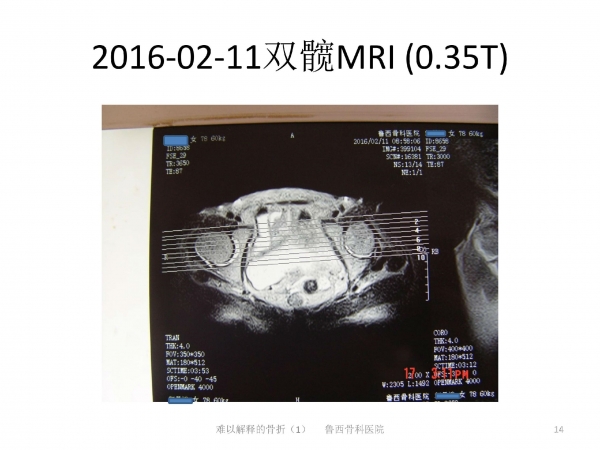

难以解释的骨折之一

导语:在日常生活中,因老年人普遍存在骨质疏松的问题,滑倒很容易造成髋部骨折。90%的老年人发生髋部骨折多因摔倒引起。然而有些骨折完全没有外伤,前驱疼痛,属于不典型骨折。来自鲁西骨科医院的王书军医师、段玉民医师,为我们带来一例“难以解释的骨折”病例,并做了初步探讨。请详见下文分解。